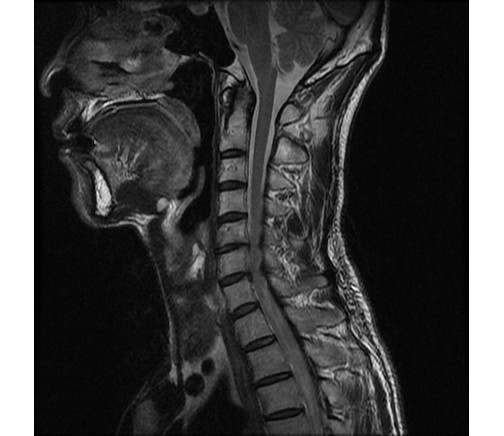

ũ ü ȸ ڴ ũ ̸ ȭ űմϴ. õ 40 Ĺ Դϴ. MRI 567 Ż̶ մϴ X - ִٰ մϴ ̸ ϰ Ӹ , ֽϴ ũ ü ȸ ڴ ũ ̸ ߿ ̸ ɰ ϴ. ȸ ̶ ̸ ֽϴ. ȸ ȸŰ ƮĪ ü ϴ. ȸ ˰ ִ ٸڼ ٸ ٸ ͵̾ϴ. õ ȸ ȭ ߽ϴ. ȭ űմϴ. ģϰ ϰ Ȯϰ ִ մϴ. [ֹȣ : 20150513180429****hw190****] * [ֹȣ : 20150514223344****hw190****] * ȣߴ Դϴ. Ű173 65 50 ()ijħ ڸǥغ ǥغ ˰Ե ͳ õ ()ijħ ڸǥغ ǥغ ϱ ȣϽ 1C.ڵӸ 1C., 1C.ټ Ǹ 1C. , 1C.̸, 6C.ڸ 6C.ھ Ḳ 5L.ڹ߹ٴ̳ ߵ ̳ ȭŸ̳ (). ġ ()ũ( ߰Ż) Ը ũ(߰Ż)ġ, , Ḳ ġ Ǵ , , Ϳ︲, ̸, Ϳ Ҹ , ȯû ô ()ijħ ڸǥغ ǥغ ϰ ߴ ġ MRI 567 Ż̶ մϴ X-ray ִֽٰ մϴ ̸ ϰ Ӹ , ֽϴ |